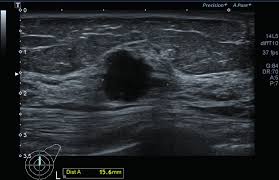

Detect slightly more cancers than a standard mammogram alone. After a mammogram that didn't show anything, and a sonogram that found the lump, i was diagnosed with stage 2 breast cancer. For example, they aren't 100% accurate in showing if a woman has breast cancer: Mammograms can also be used to check for breast cancer after a lump or other sign or symptom of the disease has been found. Breast screening with a mammogram can help to find breast cancers early when they are too small to see or feel.

Thus, approximately 20% to 28% of breast cancers are interval cancers. State that screening reduces breast cancer mortality by 20% or more, because it sounds more impressive than explaining that the absolute risk reduction is 1 in 1,000. It can find breast cancer when it is very small, even too small to feel. The current evidence suggests that breast screening reduces the number of deaths from breast cancer by about 1,300 a year in the uk. Mammograms can also be used to check for breast cancer after a lump or other sign or symptom of the disease has been found. Improve breast cancer detection in dense breast tissue. But a new study published in the new. This type of mammogram is called a diagnostic mammogram. The health professionals who take mammograms are called mammographers. Percent of women aged 40 and over who had a mammogram within the past 2 years: Not all breast cancers can be found on mammograms, especially in younger women who have more dense breast tissue. It is the best screening tool available today to find breast cancer early. The sensitivity of screening mammography in the united states is 72.4% to 80.1% 9,10;

Mammograms Why Early Detection Matters Houston Methodist On Health from www.houstonmethodist.org It is the best screening tool available today to find breast cancer early. Very early breast cancers are usually easier to treat, may need less treatment, and are more likely to be cured. The mammogram itself only takes a few minutes, but the appointment may last about 30 minutes. It can also detect calcifications Mammograms miss about 15 percent of. Breast screening with a mammogram can help to find breast cancers early when they are too small to see or feel. Studies indicate that combining a 3d mammogram with a standard mammogram can result in about one more breast cancer for every 1,000 women screened when compared with standard mammogram alone. It said 1 million women.

It said 1 million women. Little attention has been paid to how interval breast cancers are ultimately discovered. Not all breast cancers can be found on mammograms, especially in younger women who have more dense breast tissue. For women age 40 to 49: It can find breast cancer when it is very small, even too small to feel. Detect slightly more cancers than a standard mammogram alone. It's rare for women to get cancer within a year of mammography, but it does. Very early breast cancers are usually easier to treat, may need less treatment, and are more likely to be cured. Breast cancers found by screening are generally at an early stage. We estimate about 15 percent of breast cancers are diagnosed during a reasonable interval after a negative mammogram. The mammogram itself only takes a few minutes, but the appointment may last about 30 minutes. For example, they aren't 100% accurate in showing if a woman has breast cancer: Thus, approximately 20% to 28% of breast cancers are interval cancers.

Study Finds Google System Could Improve Breast Cancer Detection Voice Of America English from im-media.voltron.voanews.com For example, they aren't 100% accurate in showing if a woman has breast cancer: Improve breast cancer detection in dense breast tissue. If you have dense breast tissue, the odds of the cancer being missed on mammography start going up. But mammograms have their limits. The current evidence suggests that breast screening reduces the number of deaths from breast cancer by about 1,300 a year in the uk. The fda has now admitted that while mammography may be the best screening test to search for breast cancer, it does not find all breast cancer — especially in patients with high breast tissue density, which makes it harder to find breast cancer on a mammogram. Breast cancers found by screening are generally at an early stage. We estimate about 15 percent of breast cancers are diagnosed during a reasonable interval after a negative mammogram.